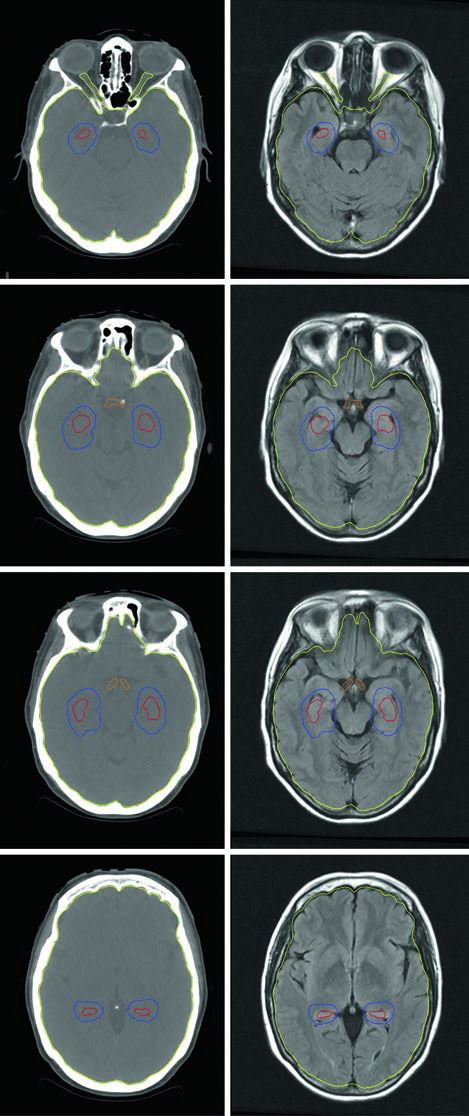

O planejamento da HA-WBRT requer IMRT com planejamento inverso, usando TC de planejamento fusionada com RM contrastada com gadolínio. A sequência utilizada é spoiled gradient tridimensional com espessura de corte axial de 1,25–1,5 mm para definir a região de exclusão hipocampal com precisão adequada. Segundo as diretrizes de contorno do RTOG 0933, apenas a porção SGZ dos hipocampos é contornada (não a estrutura inteira), e uma expansão volumétrica de 5 mm é aplicada para criar a zona de exclusão. O PTV consiste no tecido cerebral inteiro (parênquima até o forame magno) menos os hipocampos expandidos, sem margem de setup adicional.

As restrições de dose são rigorosas e variam conforme a indicação. Para metástases cerebrais: hipocampos D100% ≤9 Gy, Dmax ≤16 Gy; nervos ópticos e quiasma Dmax ≤30 Gy. Para PCI de SCLC com preservação hipocampal, os limites ficam ainda mais apertados: hipocampos D100% ≤7,5 Gy, Dmax ≤13,5 Gy; nervos ópticos e quiasma Dmax ≤25 Gy. Uma limitação importante que precisa ser avaliada na seleção do paciente: lesões localizadas a menos de 5 mm do hipocampo excluem o paciente da HA-WBRT.

A SRS de múltiplos isocentros permite tratar simultaneamente lesões em diferentes localizações — como nos lobos parietais, temporal e cerebelo — em uma única sessão de tratamento. No exemplo do livro, quatro metástases de câncer de mama (volumes de 0,07 a 1,92 cm³, diâmetros de 6 a 20 mm) foram tratadas com fração única em paciente que já recebera WBRT prévia de 30 Gy em 10 frações. O GTV de cada lesão foi definido pela captação de contraste na RM T1 pós-gadolínio, e com Gamma Knife, PTV e CTV utilizaram expansão de 0 mm a partir do GTV.